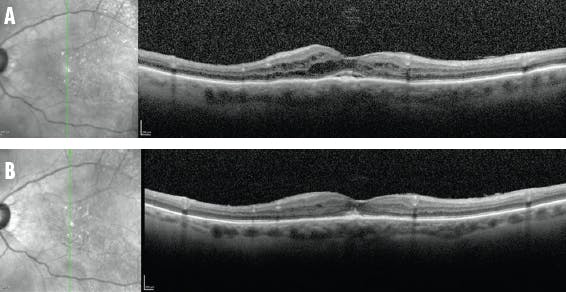

Case No. 1. An 87-year-old White woman was referred to me with chronic CME (Figure 1A). Her history included cataract extraction with IOL implantation, a selective laser trabeculoplasty, two trabeculectomies, and placement of a microinvasive glaucoma surgery device. Although one would initially avoid using a steroid implant in a patient with glaucoma, this patient had a glaucoma drainage device, a functioning trabeculectomy, and no history of a steroid response to topical or shorter-acting intravitreal steroids. Under these circumstances, I felt comfortable giving her a long-acting steroid in the form of a fluocinolone acetonide 0.18 mg implant.

The patient has done well since implantation, with vision maintained at 20/25 to 20/32 in the affected eye and no macular edema (Figure 1B). Her injection burden was reduced, from receiving an intravitreal dexamethasone implant every 2 to 4 months to receiving the one fluocinolone acetonide implant followed by two booster intravitreal dexamethasone implants over the subsequent 2 years.

<p>Figure 1. This patient with chronic pseudophakic CME (A) achieved long-term resolution of the edema after injection of a sustained-release steroid (B).</p>

Figure 1. This patient with chronic pseudophakic CME (A) achieved long-term resolution of the edema after injection of a sustained-release steroid (B).